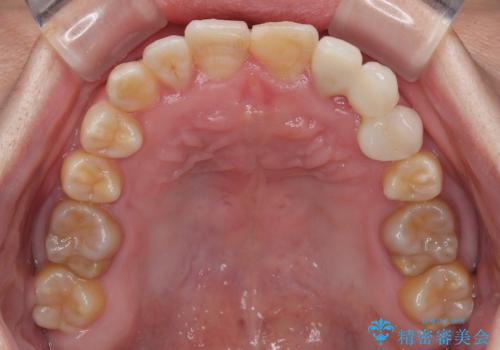

上顎が側方に拡大されて歯が並ぶスペースを確保できました。

それに伴い下顎の歯列も拡大され、舌側に倒れているのが改善されました。

左上の乳犬歯は当初保存する計画でしたが、虫歯が大きいため抜歯になり、患者様の希望によりブリッジにしました。